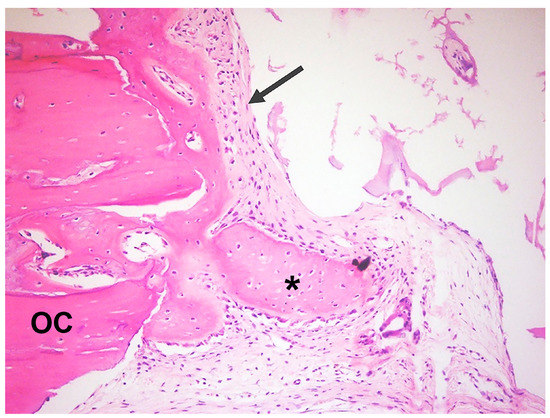

3.1. Qualitative Histological Analysis